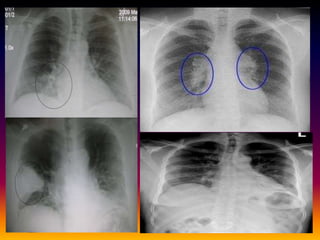

• pnemococcal lobar pneumonia:

• It is characterized by exudation of fibrinous edema fluid

into alveoli following by RBC and leukocytes many

pnemococci are also present in alveoli. This causes

consloidation of portion of lung.

• Difference b/w lobar pneumonia and

bronchopneumonia

• Lobar pneumonia

• Cased 90% by pneumococci few cases by klebsiella

pnemoniae, staph aureus.

• Occurs in otherwise healthy individual b/w 30-50 years

• Onset is sudden with high grade fever, shaking chills

and bloody or rust sputum

• Conslidation of whole lobe.

• Complication bacteremia, meningitis,endocarditis,

septic arthritis.

• Bronchopneumonia

• Caused by staphylococci streptococci, H

influenzae proteus and pseudomonas.

• Occurs infants ,old and those suffering chronic

debiliating illness or immunosuppression.

• Onset is insiduous with low grade fever and

cough productive of purulent sputum.

• Patchy pneumonic consolidation.

• Complications: fibrosis, bronchiectasis,lung

abscess.